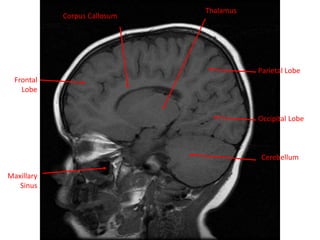

MRI BRAIN :SAGITTAL SECTIONS

White Matter

Cerebellum

Grey Matter

Frontal Lobe

Parietal Lobe

Temporal Lobe

Lateral Sulcus Occipital Lobe

Frontal

Lobe

Maxillary

Sinus

Occipital Lobe

Corpus Callosum

Thalamus

Temporal

Lateral Ventricle